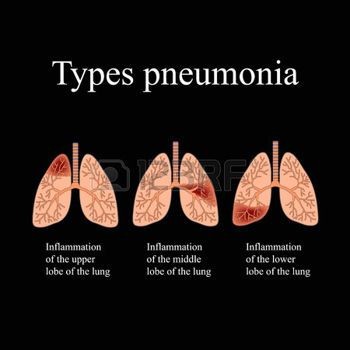

During the first few days of illness, bronchitis symptoms are similar to that of a common cold. Healthcare providers diagnose bronchitis by asking patients questions about symptoms and doing a physical examination. Though they rarely order additional tests, if you have a fever, your physician may order a chest X-ray to rule out pneumonia.